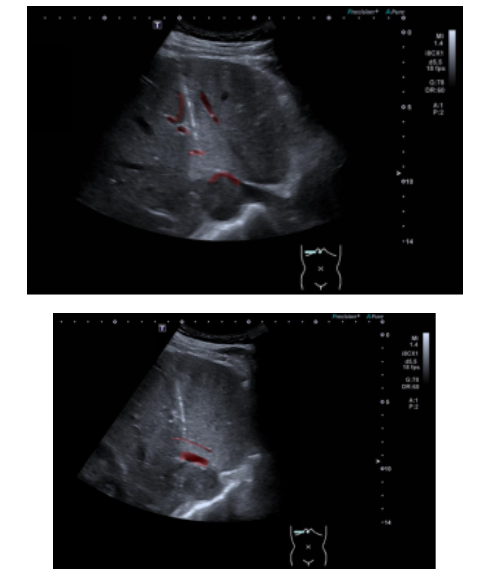

患者入住该院后,临床医师考虑到 CT 下穿刺难度大,建议其前往超声科评估是否存在超声下的安全穿刺路径。接诊后,超声科介入团队高度重视,立即对患者进行全面细致的超声影像学评估。检查发现,患者肝 S1 段占位前方有肝右静脉横亘,穿刺路径上亦有多条血管阻挡,常规穿刺路径完全行不通。经反复扫查病灶位置、大小、形态,并精准标记病灶周边血管走行与毗邻关系,团队最终锁定了唯一的安全穿刺通道。

本次穿刺由主治医师胡震主刀。在超声实时动态引导下,胡震屏息凝神、稳扎稳打,手持穿刺针在超声影像的「导航」下,沿着术前规划的精准路径缓缓推进。全程紧盯屏幕,实时调整进针角度,在错综复杂的血管缝隙中「穿针引线」。每一步推进都精准到毫米,完美避开所有高危血管,准确命中病灶无血管遮挡的边缘部分。